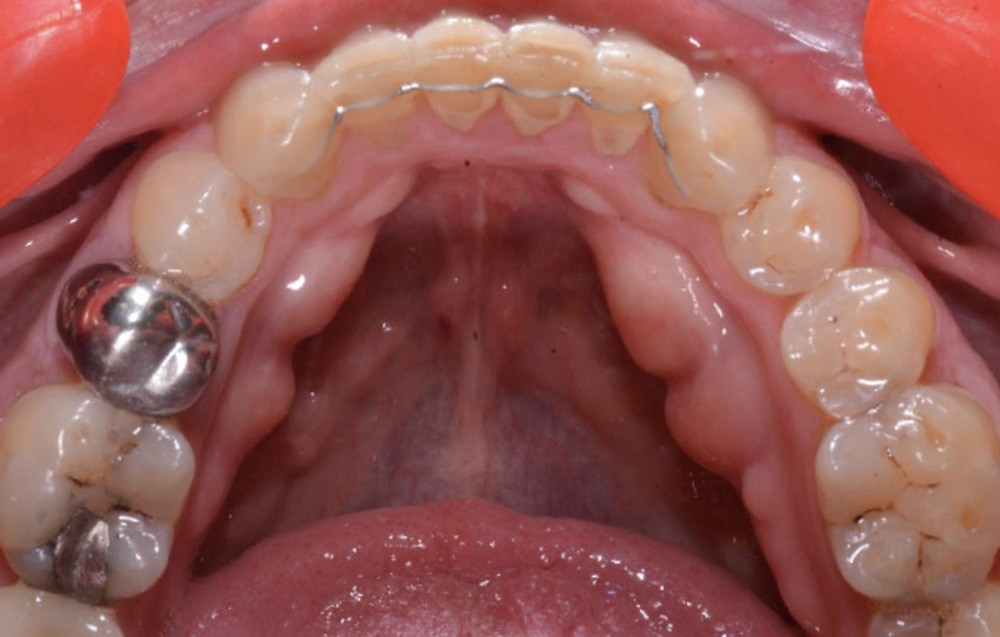

(fig. 4 à 10)

Le plan de traitement établi conjointement avec son chirurgien-dentiste traitant consiste à réaliser un alignement dentaire mandibulaire et à réaliser des extractions de 16 et 15 pour un remplacement par prothèse implanto-portée.

La durée orthodontique prévue est de neuf mois, avec comme contrainte principale l’absence de possibilités de modification des formes d’arcades.

Le gain de place se fera par des réductions interproximales sur la zone incisivo-canine mandibulaire.

Il est décidé de ne pas redresser la 43 complètement afin de ne pas entraîner d’interférences occlusales.

Un accompagnement par des meulages occlusaux est réalisé.